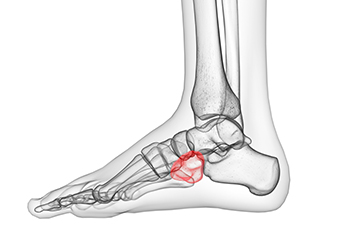

Cuboid fractures are rare and occur when the cuboid bone in the foot becomes broken. The cuboid bone is one of the smallest bones in the foot, and when it breaks, it can cause pain and trouble walking. Cuboid syndrome is a condition that is related to the cuboid bone. It happens when the cuboid bone does not move or function properly. This can cause pain on the outer part of your foot and make it hard to walk. Sometimes, cuboid syndrome can occur after a cuboid fracture because the bone may not heal correctly, or may still be out of place. If you have foot pain on the outer side of the foot, it is suggested that you schedule an appointment with a podiatrist to obtain a proper diagnosis and treatment that will help you return to normal activity as quickly as possible.

Cuboid syndrome, also known as cuboid subluxation, occurs when the joints and ligaments near the cuboid bone in the foot become torn. If you have cuboid syndrome, consult with David Mehl, DPM from New York. Our doctor will assess your condition and provide you with quality foot and ankle treatment.

Cuboid syndrome is a common cause of lateral foot pain, which is pain on the outside of the foot. The condition may happen suddenly due to an ankle sprain, or it may develop slowly overtime from repetitive tension through the bone and surrounding structures.

A common symptom of cuboid syndrome is pain along the outside of the foot which can be felt in the ankle and toes. This pain may create walking difficulties and may cause those with the condition to walk with a limp.

Diagnosis of cuboid syndrome is often difficult, and it is often misdiagnosed. X-rays, MRIs and CT scans often fail to properly show the cuboid subluxation. Although there isn’t a specific test used to diagnose cuboid syndrome, your podiatrist will usually check if pain is felt while pressing firmly on the cuboid bone of your foot.